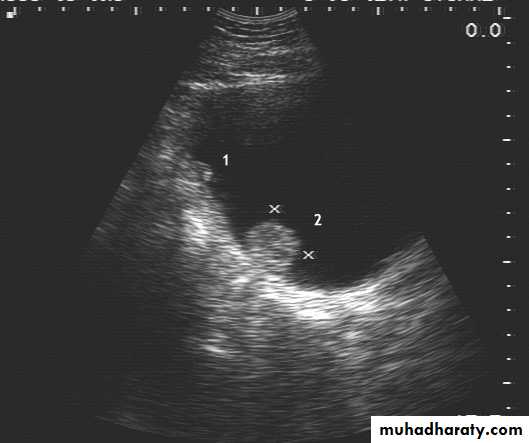

US :-

shows echo-free cystic lesion with posterior enhancement.